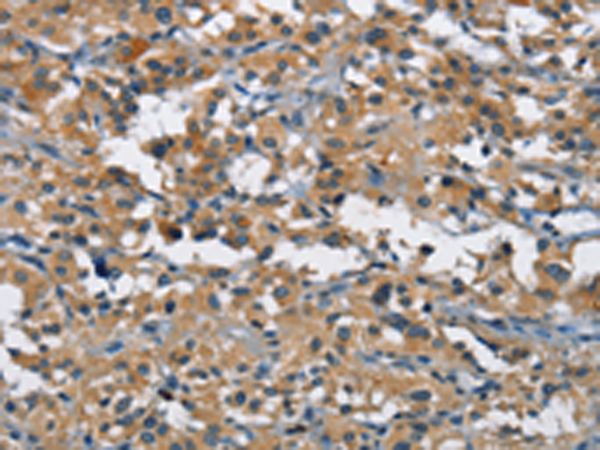

分类: 科研抗体货号: P07134别名: ALK6; ALK-6; CDw293应用: IHC反应种属: Human, Mouse